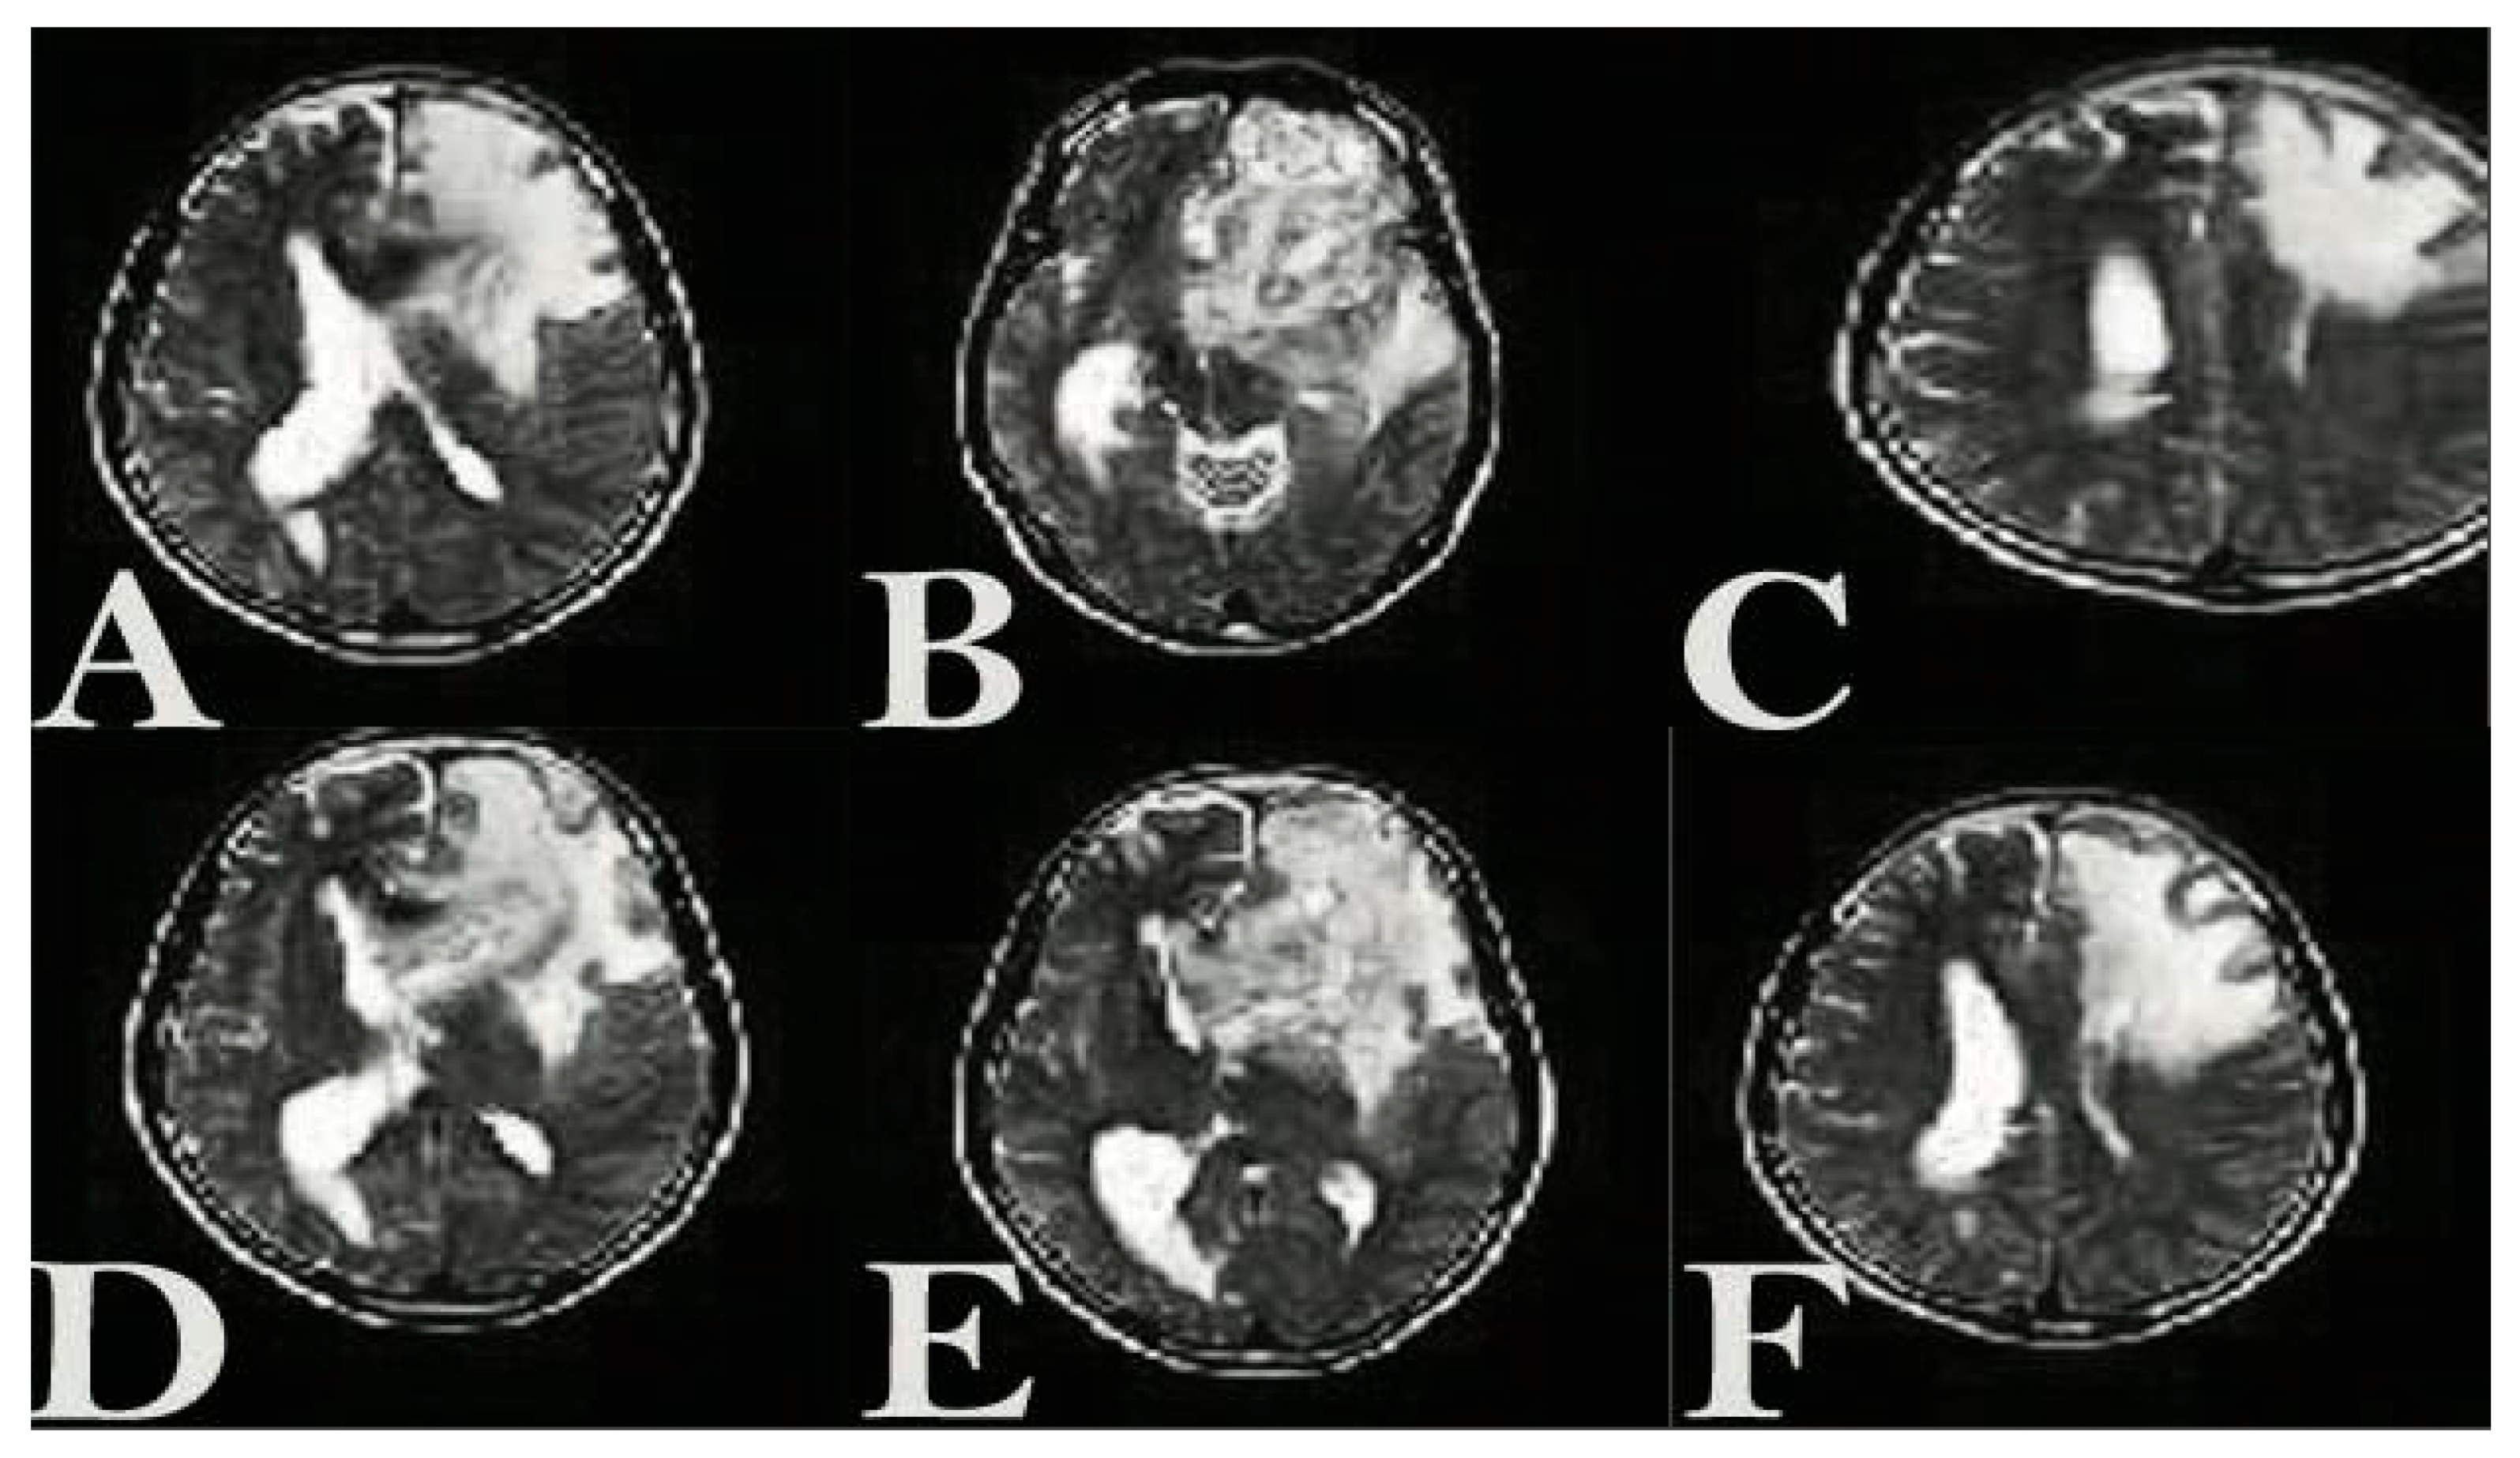

3.3. The Presence of NLP-EXOSOME COMPLEX Formulated Stat3 Silencer, Leads to an Increase in the Overall Survival Rate and a Decrease in Tumor Size in Mice with Glioma

3.4. The Presence of NLP-EXOSOME COMPLEX Resulted in a Decrease in the Expression of STAT3 Within the Tumor